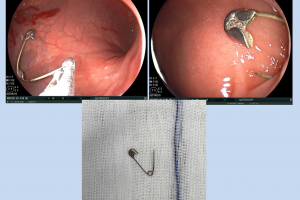

Vừa qua Bệnh viện Nhi Đồng Thành Phố tiếp nhận một trường hợp trẻ V. T. KH. 7 tuổi, nam, ngụ ở Đồng Tháp. Khai thác bệnh sử ghi nhận cùng ngày nhập viện, trẻ...